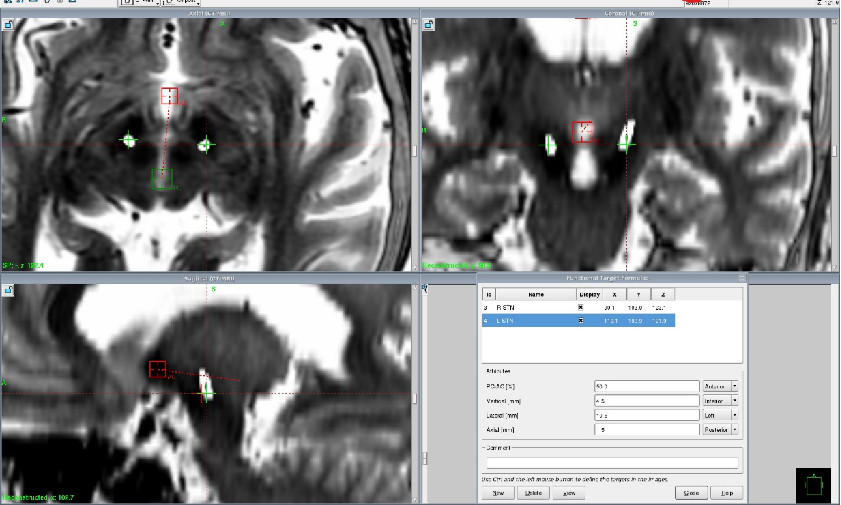

术后CT与术前MRI融合,电极位置准确

术后电极位置三维重建,电极触点位于STN核(lead DBS)